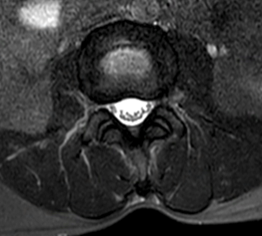

病患B右圖脊椎MRI橫切面腰椎3-4節顯示正常椎管空間。

診斷以病史與神經學檢查 為主。當臨床懷疑神經受壓、症狀持續或需規劃介入/手術治療時,醫師常會安排 MRI(磁振造影) 或必要時的 CT,以確定壓迫的節段、程度與合併病變(例如椎間盤突出或滑脫)。